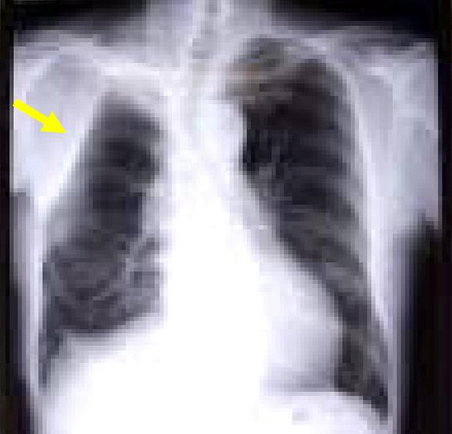

左肺癌の画像所見

胸部XP(左上肺野に腫瘤影あり)